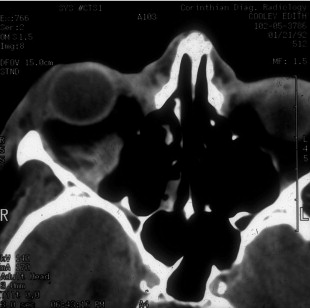

Once the diagnosis of retrobulbar hemorrhage is made, the treatment requires immediate attention. The first step should be to identify those hemorrhages that require medical or surgical care, based upon the ophthalmic examination. If the intraocular pressure is elevated, topical and systemic glaucoma medications are utilized. Systemic corticosteroids are used for significant edema. When the bleeding threatens the visual system, or is worsening, surgical therapy is required. The incision is opened widely through the orbital septum and the surgical site and orbit are explored for signs of bleeding. Clots are evacuated and cautery is applied. If the condition remains unresponsive, a lateral canthotomy and cantholysis is performed. In severe cases, both the inferior and superior crus of the lateral canthal tendon can be released. When these measures fail, an emergency CT scan without contrast is warranted. If posteriorly organized hemorrhage is identified, bony decompression may be warranted to relieve orbital apex compression ( Figure 14.3 ). The treatment should be aggressive for the first 24–48 h post-operatively.